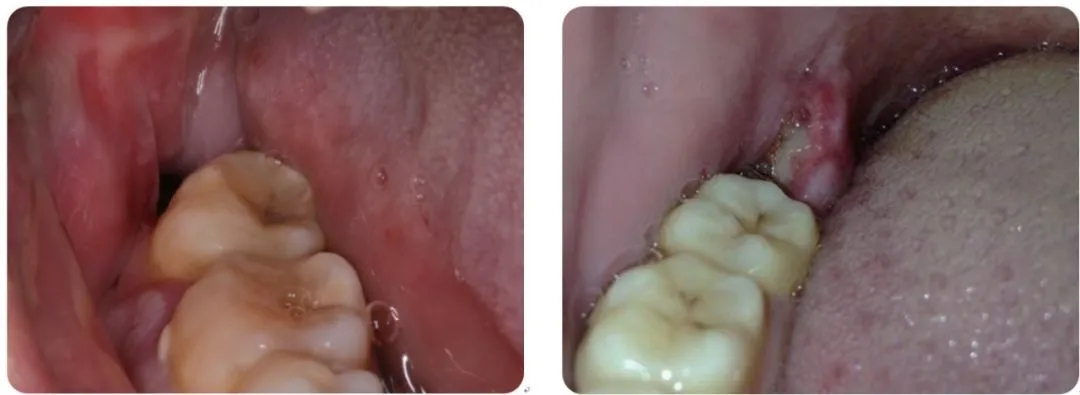

一种拔牙后并发症,最早由Crawford 报道于1896 年。简单理解为拔牙后血凝块脱落,牙槽窝干燥,牙槽骨暴露于充满细菌的口腔中,而发生骨壁感染。

它是复杂牙拔除后疼痛严重的并发症,最常见发生于下颌阻生智齿拔除后。发生率依次为:下颌第三磨牙、下颌第一磨牙、下颌第二磨牙,其他牙少见,前牙发生率最低。